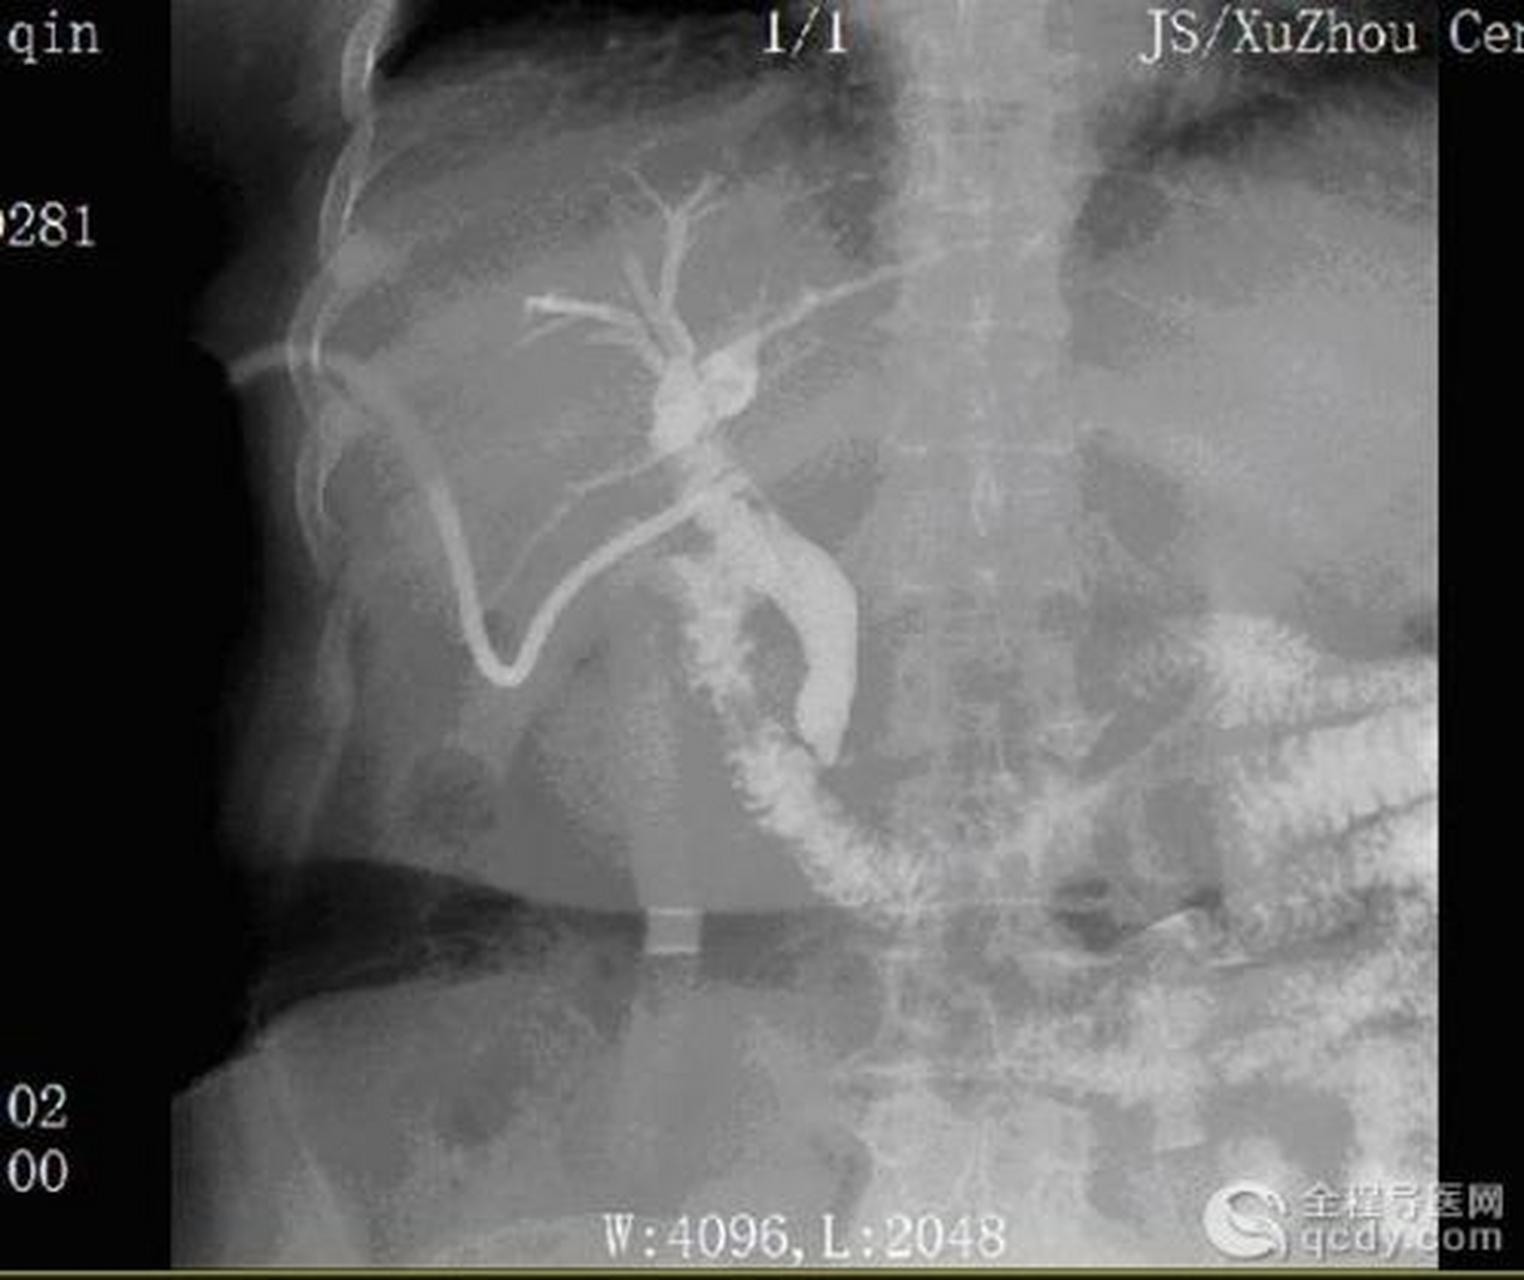

造影剂注入后,胆内外胆管显影.远端梗阻,肝内胆管明显扩张,迂曲

术中胆管造影显示肝内胆管和胆总管上段严重扩张,胆总管中段胆管占位

术中造影示胆总管中段显影中断,胆总管上段,肝内胆管及胆囊扩张明显